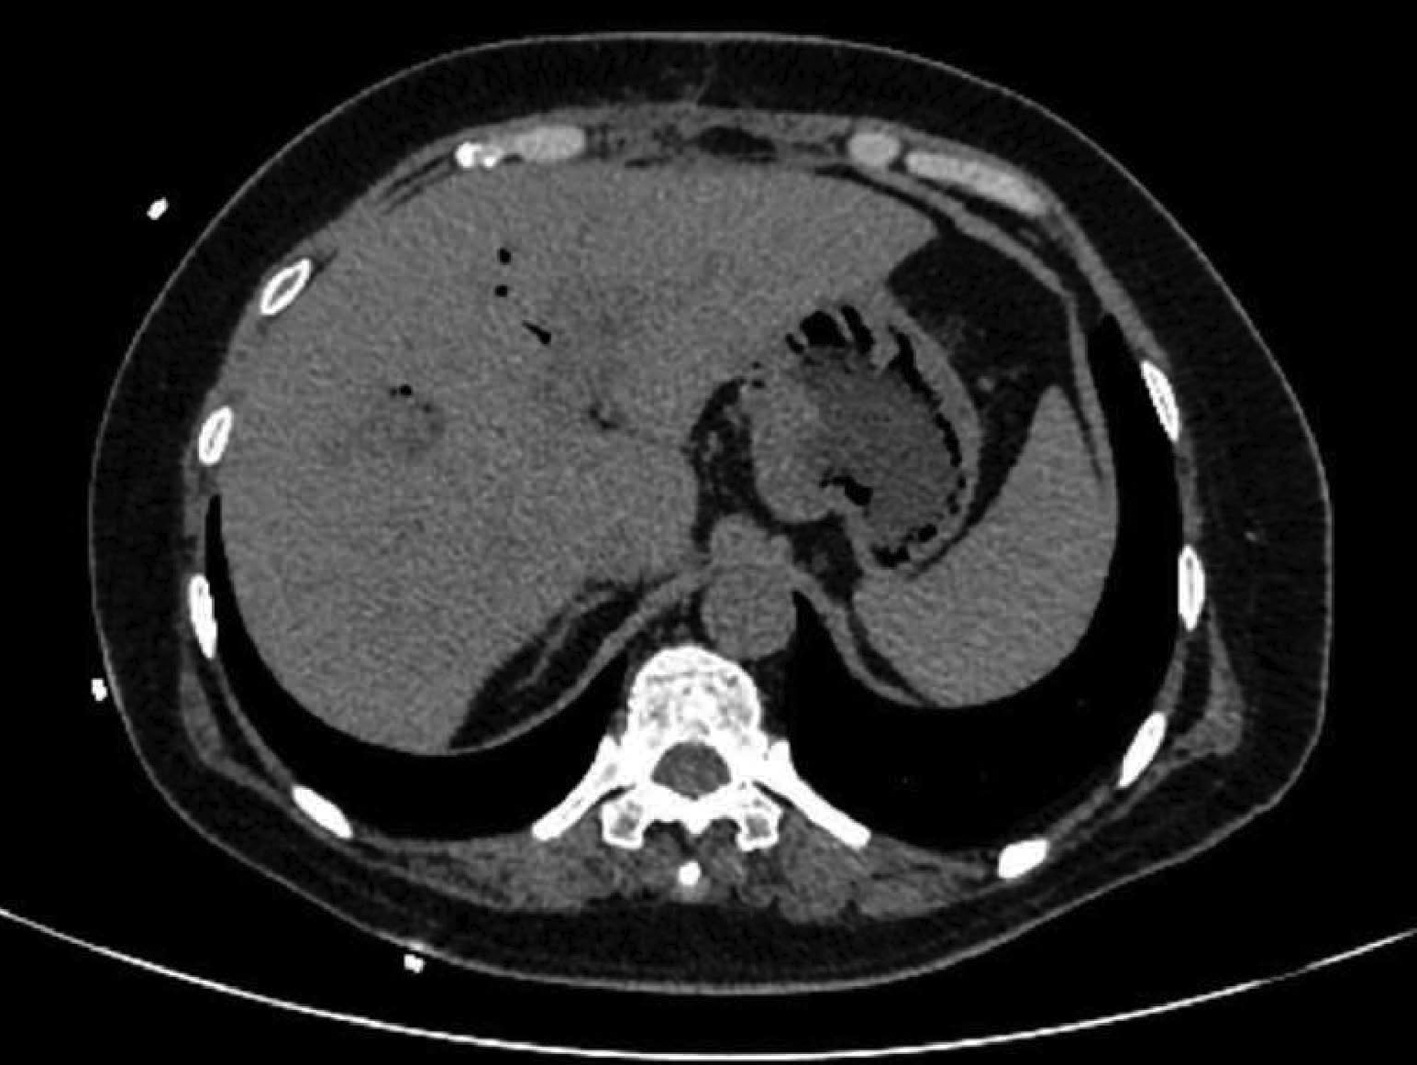

Spontaneous rupture of biliary dilatation with cancer: A case report

Xiaotong QIU, Zhengqi WU, Yushi CAO, Xuxiang XIA, Guoyue LYU

2022, 38(5): 1129-1130. DOI: 10.3969/j.issn.1001-5256.2022.05.031

Abstract(907) HTML (321) PDF (2537KB)(30)

Abstract: